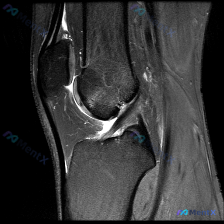

刚刚整理了一份很有启发的膝关节MRI读片病例,分享给大家,这个病例最有意思的点就是预设问题和实际影像发现不一致,很考验读片思路。 病例基础信息 这是一张膝关节矢状位T2加权MRI图像,需要评估是否存在半月板异常,图像质量清晰,能看到股骨远端、胫骨近端、髌骨、髌下脂肪垫、关节间隙等全部关键结构。 影像...

看到这张膝关节MRI矢状位T2序列的影像,整理一下分析思路,和大家一起讨论。 先整理影像核心发现 这是单张膝关节MRI矢状位T2序列影像,核心异常如下: 1. 骨骼结构:股骨远端、胫骨近端、髌骨轮廓完整,无明显骨皮质断裂 2. 韧带:前交叉韧带(ACL)走行可见,但近股骨附着点和中段低信号连续性不佳...